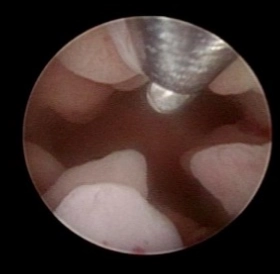

当院では子宮鏡検査で、子宮内膜ポリープ、小さな子宮粘膜下筋腫、子宮内癒着、慢性子宮内膜炎によるマイクロポリープを認めた患者様に対する子宮鏡手術として、Hologic社の『MyoSure』を用いて、年間500例以上の子宮鏡手術を行っております。

一般的な子宮内膜ポリープの摘出方法は、ループ状の電気メスや鉗子を用いて切除するため、子宮内膜の熱損傷や、正常な内膜まで損傷してしまうリスクがあります。

『MyoSure』は、細い子宮鏡で子宮内を確認しながら、病変を少しずつ切断して摘出するため、子宮内膜へのダメージがありません。